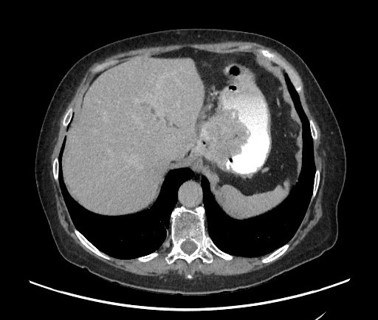

With extreme caution and under strict endoscopic control, traction is applied (Figure 4) to the material, achieving en bloc extraction (Figure 5). A CT scan was performed, ruling out complications (Figure 6). The patient was discharged after 4 days asymptomatic, with normal outpatient endoscopic follow-up.

Figure 6: hanges consistent with Nissen fundoplication, showing thickening and inflammatory alterations. No contrast extravasation or extraluminal gas bubbles observed.

Figure 6